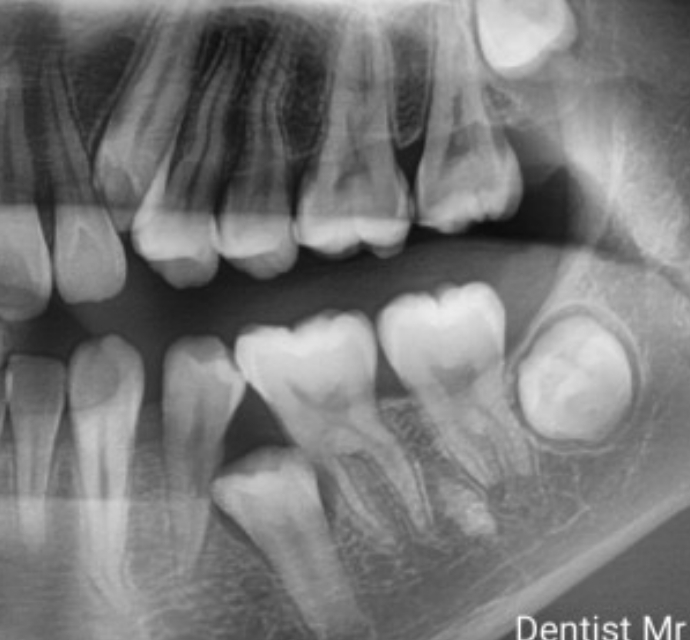

国每年都有不少人患上龋齿,不仅有儿童,也有不少大人因为龋齿问题而痛苦。而部分病情不严重的龋齿,可以采取补牙的方式补救。树脂充填是一种较为人们所熟悉的补牙材料,但是不少人也比较担忧树脂的使用时长及是否有毒等问题,到底为什么补牙要用树脂充填?

树脂材料是现在补牙最常规的材料,一般医生在治疗龋齿的时候会把洞制作成口小底大的形状,树脂固化以后没有其他问题的情况下一般是不会脱出的。因此质量还是不错的,当然,也需要诊所良心,选用的材质是符合规定的。

然而,对于龋坏较为严重的大面积缺损的牙,牙体修复后往往由于牙体本身抗力不足,在咀嚼时易发生牙折,因此在补牙之前最好确认缺口的大小,然后选择适合的方式。